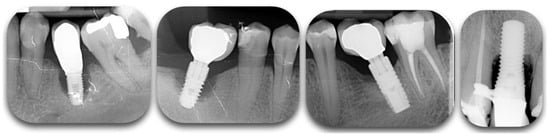

Figure 2.

Radiographic films showing different degrees of peri-implant bone loss. The change of contrast can make the defect difficult to categorize.